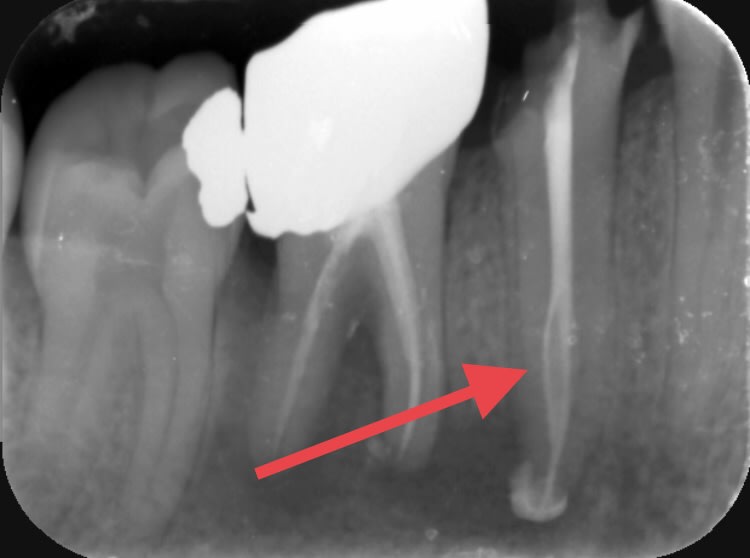

Pxav toi qui aimes bien faire des dépassements de ciment . Regarde moi ce 2eme canal obturé. Est-ce que ça ne te troue pas les fesses ? Est-ce que t’arrives à obturer un 2eme canal comme ça toi?:)